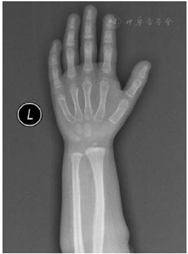

实验室及影像学检查:血常规、肝肾功能、电解质、心肌酶、血脂、血糖未见异常;甲状腺功能3项〔促甲状腺激素(TSH)、游离甲状腺素(FT4)、游离三碘甲状腺原氨酸(FT3)〕未见异常;促肾上腺皮质激素、皮质醇、17羟孕酮未见异常;染色体核型分析:46XX;微量元素6项(锌、铁、钙、镁、铜、铅)未见异常;25-羟基维生素D 89.63 μg/L。精氨酸联合左旋多巴激发试验生长激素(GH)峰值3.87 μg/L(>10 μg/L为正常),胰岛素样生长因子1(IGF-1)104 mg/L,胰岛素样生长因子结合蛋白3(IGFBP-3)3.62 mg/L。心脏彩超提示:房间隔卵圆孔未闭0.34 cm。肝胆胰脾双肾未见异常,肾上腺B超未见异常。左手腕骨X线片示:骨龄2岁,CSE伴指骨弥漫性缩短(图1)。脊柱正侧位片示:脊柱生理曲度可,无明显侧弯。颅脑+垂体磁共振成像(MRI)无异常。